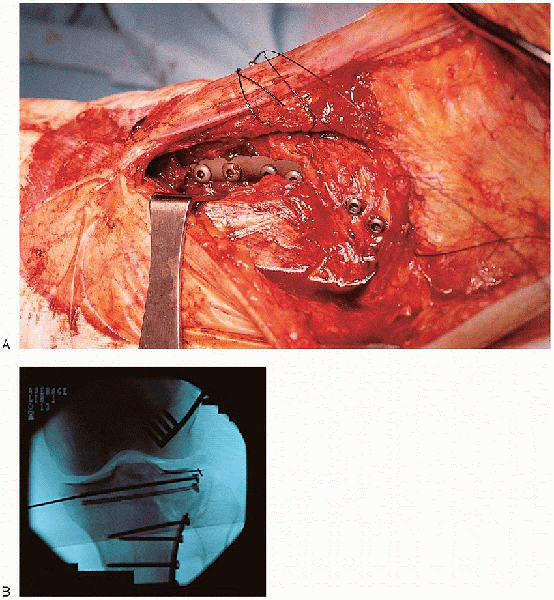

stabilization is performed. Definitive stabilization requires the

insertion of two 6.5- or 7.0-mm cancellous lag screws parallel to the

joint (Fig. 30-17), followed by metaphyseal buttress plating (Fig. 30-18).

This buttress must be located at the distal extent of the fracture line

and serves to prevent shear forces from causing late collapse. The

choice of plates depends on the degree of cortical comminution and may

be as simple as a washer (i.e., one-hole plate), two-hole plate, T- or

L- buttress plate, or Burri plate. The surgeon should select that plate that offers stable fixation but minimizes bulk to prevent complications with wound closure.

irrigated and the wound closed. The coronary ligament of the knee

capsule is reattached using sutures or Mitek anchors, or both (Fig. 30-19). Wound closure is performed over suction drains. If the wound cannot be closed without tension, it is

![]() |

|

FIGURE 30-17. A to C: Placement of lag screws across the split fracture component.

FIGURE 30-18. A and B: Placement of the lateral buttress plate.